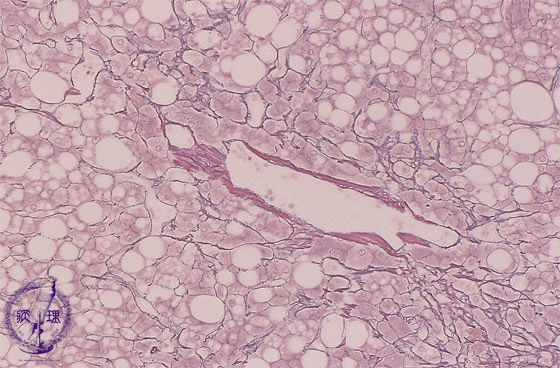

Microscopic image (silver stain, high power): Centrilobular hepatocytes demonstrate pericellular fibrosis and central vein walls are thickened. There is macrosteatosis.